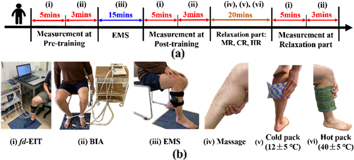

2.2. Experimental protocol and conditions

Twenty-four healthy young men (age: 30.0 ± 3.0 years, height: 173.5 ± 6.5 cm, skeletal muscle mass: 35.6 ± 6.8 kg) volunteered for this study. None of the subjects had any history of any musculoskeletal or neurological disorders. Figure 2 shows the experimental protocol consisting of four parts: pre-training, training, post-training, and relaxation parts (Zainuddin et al 2005). In all experimental protocols, subjects were measured in a sitting position.

Figure 2. (a) Experimental protocol. (b) The specific steps in the experimental protocol using (i) fd-EIT, (ii) BIA, (iii) EMS, and relaxation methods of (iv) massage, (v) cold pack, and (vi) hot pack.

Standard image High-resolution imageIn the pre-training part, firstly, fd-EIT is conducted to reconstruct the conductivity distribution images σ pre in the human right calf; secondly, BIA (Inbody S10, InBody Co., Ltd, Korea) measures the extracellular water ratio βp = ECW/TBW, which is compared with the conductivity distribution change. Figure 3 shows the 16 electrodes of the fd-EIT sensor location and distribution.

Standard image High-resolution imageIn the training and post-training parts, firstly, the subject's calf muscles are stimulated by EMS for 15 min using commercial EMS equipment (SIXPAD Leg belt, Nagoya MTG Ltd, Japan); secondly, fd-EIT is conducted to reconstruct the σ post in the human right calf; finally, BIA is used to measure βp . Figure 4 shows the position of the EMS electrode, which contacts the subject's skin directly. The EMS equipment in this study has a different voltage value but uses a constant-controlled current, which is 8 mA. The stimulation cycle rule is a 4 s stimulation with 4 s pause and the stimulation frequency is 20 Hz. After testing the EMS tolerance limit of each experimental subject, level 10 of EMS training intensity was selected from twenty training levels of EMS in situ. Level 10 means that the EMS output voltage is 26.13 V.

Standard image High-resolution imageIn the relaxation part, the subjects' calf muscles were relaxed for 20 min by three methods of relaxation. The twenty-four subjects were divided into the massage relaxation (MR) group, cold pack relaxation (CR) group, and hot pack relaxation (HR) group with eight subjects per group. A water bag at around 12 °C was used to relax the subjects' calf muscles in the CR group. A towel soaked in hot water (temperature around 40 °C) was used to relax the subjects' calf muscles in the HR group. The temperatures of the water bag and towel were controlled by a temperature gun (the given error was ±5 °C). After relaxing, firstly, fd-EIT was conducted to reconstruct σ relax in the human right calf; finally, BIA was used to measure βp .